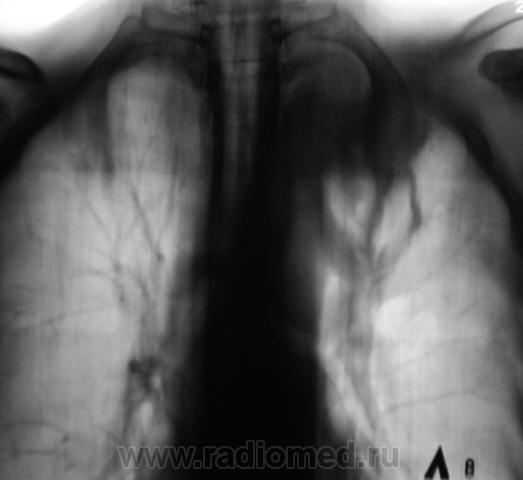

Нужна клиника. Частично опрожнённая лёгочная киста ?

Мне кажется, что это образование. От корня отходят, вероятно, расширенные сосуды.

А мне кажется, что это фиброзная каверна в цирротечески изменённой верхней доле.

Похоже, с уровнями. Заячьи ушки). Более молодой детёныш и в правой верхушке.

в правом лёгком и вокруг полости есть. Туберкулёз. Палочки Коха должны сыпаться в изобилии. На фиброзно-кавернозный и цирротический не дотягивает, так как выраженного  смещения прилещих органов  с сторону поражения нет. Полость раздута. Насчет формы туберкулеза можно очень долго спорить. Динамика покажет.  Главное - есть туберкулёз или нет туберкулёза. Спасибо за демонстрацию. Nik

Полость дренируется-это не рак.Либо каверна, что вероятно; либо абсцесс, что тоже может быть.